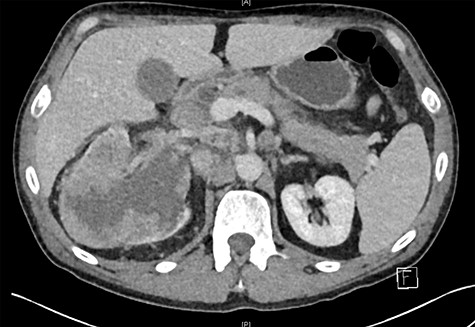

A retroperitoneal percutaneous biopsy of the retrocaval lymph node mass was performed without any complications. Awaiting histological diagnosis, his gastric outlet obstruction worsened, and hyperbilirubinemia increased to 317 umol/L, developed acute renal failure with creatinine rising to 484 umol/L and progressive anuria. The renal failure was believed to be multifactorial from malignancy and cholemic nephropathy that can be seen in patients with obstructive jaundice [2]. The patient was transferred to HDU (High Dependency Unit) for haemodialysis. Histopathology results confirmed a poorly differentiated high-grade RCC of clear cell subtype. Endoscopic examination performed confirmed an infiltrating obstructive duodenal mass and a self-expanding ‘Wallflex’ duodenal stent was inserted. As retrograde access for biliary stenting was near impossible, a percutaneous transhepatic cholangiography (PTC) was performed with anterograde stenting of the bile duct resolving the hyperbilirubinemia (Fig. 3). Over the following days the patient’s hyperbilirubinemia and renal failure normalized. He recovered uneventfully and was subsequently commenced on immunotherapy prior to discharge.

(PTC) Anterograde biliary stent through duodenal wall flex stent.